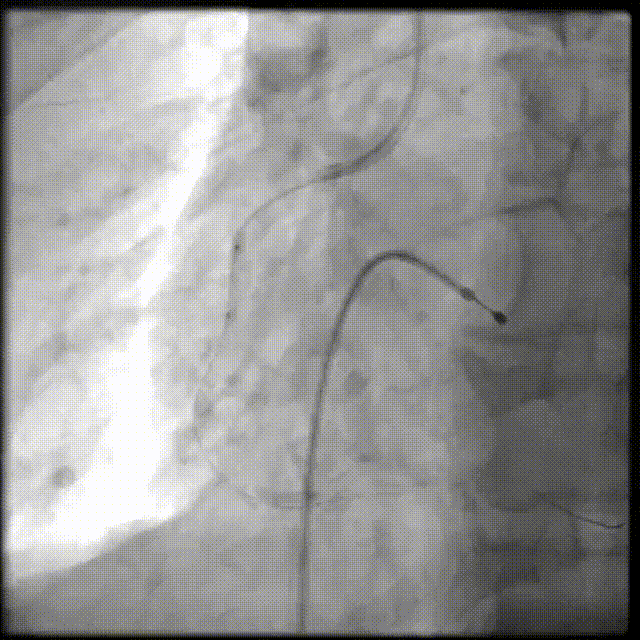

PCI过程-冲击波球囊PTCA

沿导丝送3.0×12mmGennWave冲击波球囊至RCA严重钙化病变处,充盈1:1比例造影剂盐水,以4atm低压扩张,每周期给予10秒、每秒1次血管内冲击波治疗后扩张至6atm,共进行8周期血管内冲击波治疗。

PCI过程-球囊PTCA

冲击波球囊完成后,进一步预处理,依次应用非顺应性球囊 2.75X15mm、非顺应性球囊 3.0X15mm、切割球囊 3.0X10mm等球囊反复由远及近进行扩张。